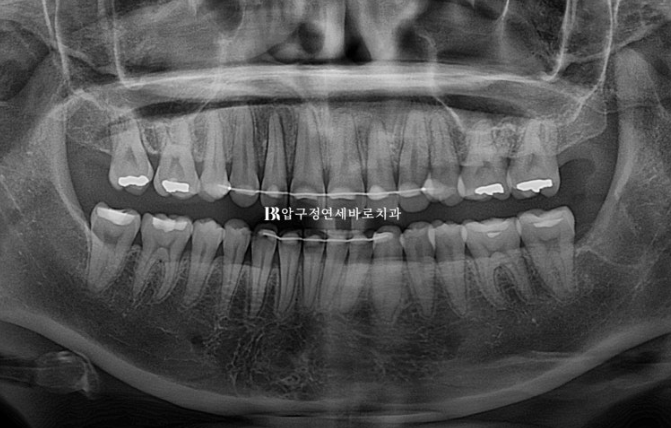

23.08

24.12

발치 공간으로 어금니 쓰러짐 없이 뿌리까지 평행하게 이동 된 것이 확인됩니다.

인비절라인으로 뿌리이동 안되나요?

아니요 잘 됩니다